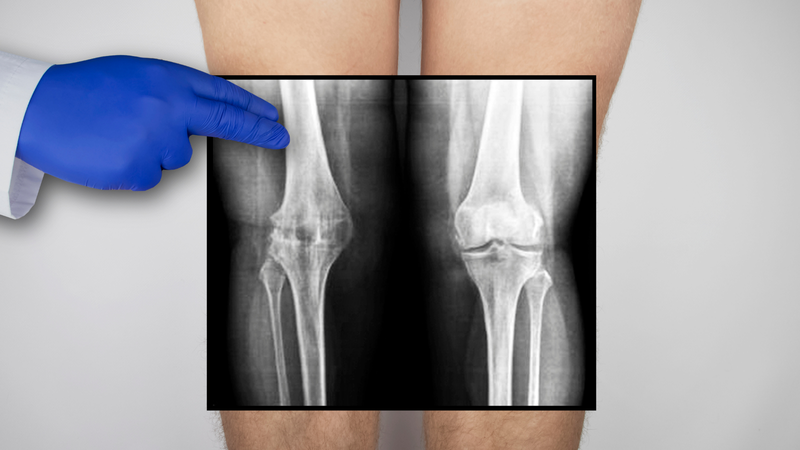

Chụp cộng hưởng từ (MRI) khớp gối là một phương pháp chẩn đoán hình ảnh hiệu quả, giúp phát hiện chính xác các tổn thương liên quan đến khớp gối như đứt dây chằng chéo trước (ACL).

So với các phương pháp khác, X-quang chỉ đánh giá được tổn thương xương, trong khi siêu âm có thể gặp hạn chế khi quan sát dây chằng do khó phát hiện tụ dịch hoặc tổn thương nhỏ. Một dây chằng chéo trước khỏe mạnh sẽ có các bó sợi liên tục từ mâm chày đến xương đùi, đây cũng là tiêu chuẩn để đánh giá tình trạng bình thường của dây chằng trên hình ảnh MRI.